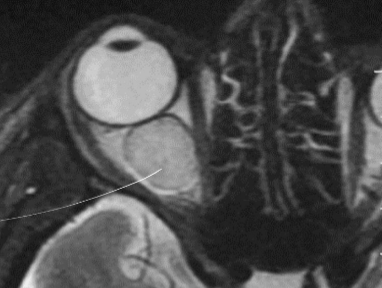

Retinoblastoma

Tumor maligno primario de la retina

- Clx: leucocoria - pupila blanca

Estudio de imagen retinoblastoma

Calcificaciones intraoculares

- TC: ver calcificaciones

- RM: mapeo del tumor

- US: ultima opcion si no hay tc o rm